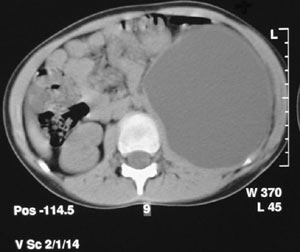

Εικόνα

3. Μπλε: Καθετήρας Blue Stent. Κόκκινο: Αναστόμωση πυέλου και ουρητήρα.

4. Υπερηχογράφημα (διάταση πυέλου και καλύκων, παρουσία υγρού στα

δεξιά της εικόνας).

5. Αξονική Τομογραφία κοιλίας. Ευμέγεθες ουρίνωμα αριστερά (δεξιά

στην εικόνα).